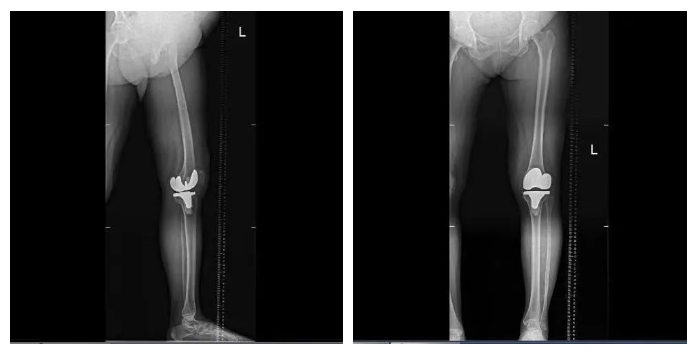

手術(shù)全程操作流暢高效,通過術(shù)后測(cè)量顯示,實(shí)際截骨量、術(shù)后下肢力線與術(shù)前規(guī)劃完全一致,真正實(shí)現(xiàn)了高效和精準(zhǔn)。此外,鴻鵠?的自動(dòng)定位截骨功能,避免了傳統(tǒng)手術(shù)中采用髓內(nèi)定位工具可能會(huì)對(duì)患者髓腔造成一定損傷等問題,很大程度減少了軟組織和骨組織的損傷,患者出血少、創(chuàng)傷小,術(shù)后膝關(guān)節(jié)功能的康復(fù)更快。據(jù)悉,患者術(shù)后恢復(fù)良好,第二天即可進(jìn)行早期功能鍛煉。

▲患者術(shù)后平片